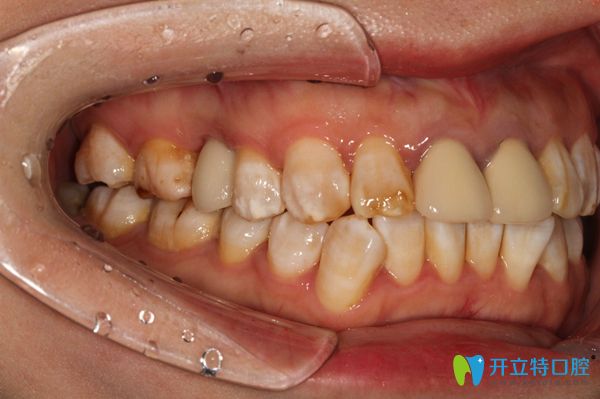

放完種植體之后,醫(yī)生給錢女士戴的是臨時的牙冠,因為錢女士的口腔情況不適合即刻種植,所以,她需要三個月以后再來戴真正的牙冠。做完種植牙后,錢女士開心的說:“覺得自己年輕時候的那種咀嚼功能,又回來啦,真舒服”。

▲這是錢女士在廣州陽光樹口腔戴上真正的牙冠后的樣子喲!